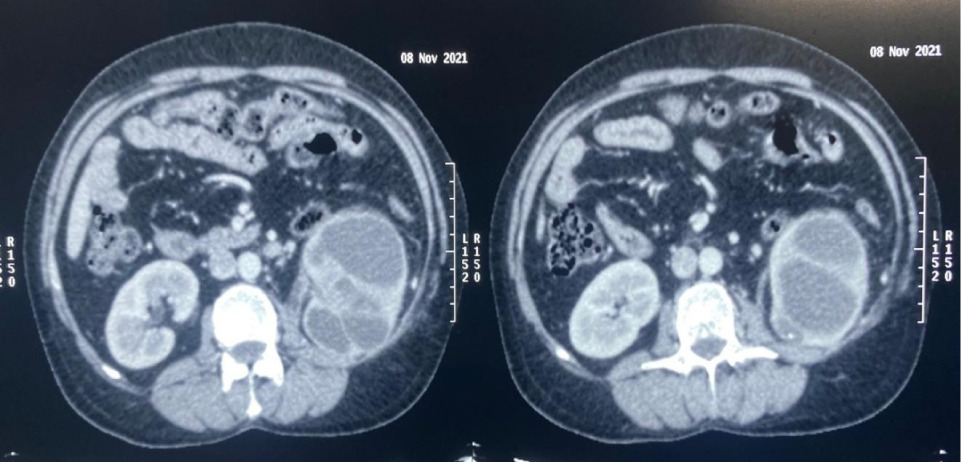

The patient was admitted, and third-generation cephalosporins were started. Blood culture and urine culture were sent. He had raised counts of 24,500/mm3 with a creatinine of 1.1. Ultrasound showed left-sided gross hydronephrosis with multiple echoes, and CT urography showed a left hydronephrotic kidney with no obvious obstructive calculus (Figure 1).

Figure 1: First computed tomography urography.